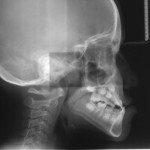

Thin-Plate Spline dei cambiamenti morfologici mandibolari

Thin-Plate Spline dei cambiamenti morfologici mandibolari indotti dal trattamento precoce delle classi III: valutazioni a lungo termine

Candidato: Silvia Cerroni

Relatore: Prof.ssa Paola Cozza

Obiettivo

L’obiettivo del nostro...